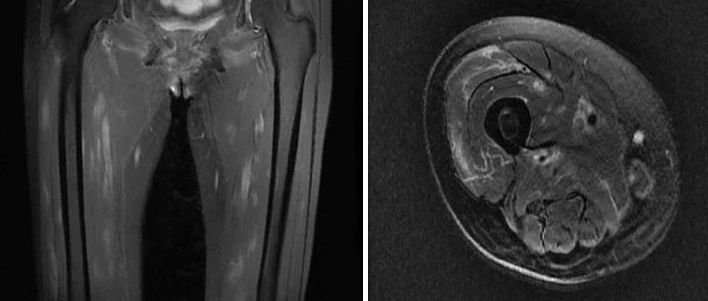

感谢丁香园论坛达人 @好奇先生的手術室 分享的优质病例~简要病史:患儿主因「自觉双足无力 3 天,双下肢无力 2 天」入院。患儿于 3 天前无明显诱因出现双足无力,不伴麻木,未予特殊处理;2 天前出现双下肢无力,伴小腿部酸痛,可站立,能短距离独立行走但步态不稳。行走时抬脚费力,不能蹲下,无头痛、发热,无咳嗽、咳痰。查体:扁桃体 I° 肿大,颈软,双肺呼吸音粗,未闻及干湿性啰音;双下肢远端肌力左侧 2 级 +,右侧 2 级,肌张力正常;双下肢无水肿,双侧膝腱反射正常存在,布氏征、克氏征阴性,双侧巴氏征阴性。...